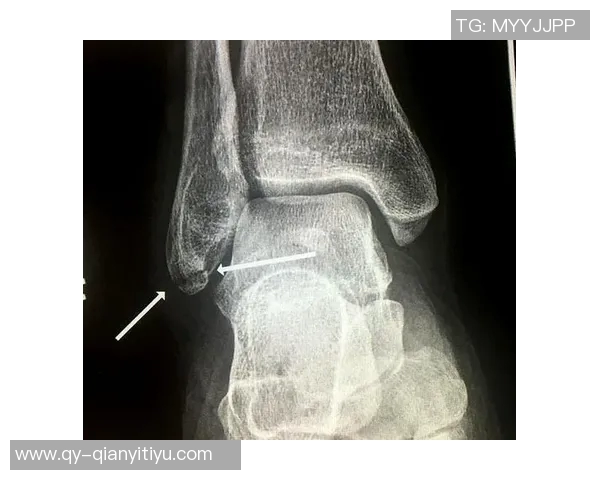

小卡·伦纳德是一位备受瞩目的篮球明星,但他的职业生涯却因频繁受伤而受到影响。最近,他再次因为脚踝的问题缺席比赛,这让球迷和球队都感到忧虑。弗兰克在接受采访时表示,小卡的伤势不仅仅是简单的扭伤,而是可能涉及到更深层次的问题,比如韧带和软组织损伤。

具体来说,小卡在比赛中的高强度对抗使得他的脚踝承受了巨大的压力,而这些压力往往会导致微小的损伤逐渐累积。他提到,小卡之前已经经历过几次类似的情况,这些旧患可能会加重他当前的状况。因此,对于一个顶级运动员来说,及时准确地判断并处理这些问题至关重要。

此外,弗兰克还强调了医疗团队在这一过程中扮演的重要角色。他们需要通过专业评估来确定最佳治疗方案,并确保小卡能安全复出。而球员自身也要更加重视身体信号,以防止日后更严重的伤害发生。